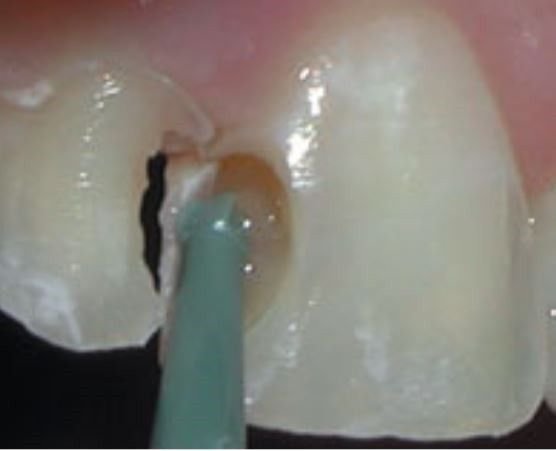

Sistema de Easy para remover caries

Sistema diseñado con fresas de polímero que están desarrolladas para eliminar la lesiones cariosas, realizando un desgaste selectivo de las caries, la fres “inteligentemente” se va desgastando, debido a que la dureza superficial de la dentina sana va aumentando cpmfprme se elimina el tejido carioso.

Este kit consta de 6 fresas inteligentes que son:

C43 FRESA INTELIGENTE BOLA NO. 4 CONTRANGULO (dos piezas)

C44 FRESA INTELIGENTE BOLA NO. 6 CONTRANGULO (dos piezas)

C45 FRESA INTELIGENTE BOLA NO. 8 CONTRANGULO (dos piezas)